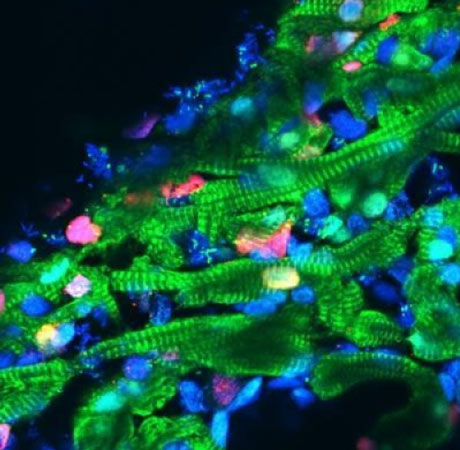

জেব্রাফিশের হার্টের ‘ইসিএম’ (সবুজ)

নতুন ভাবে তৈরি হওয়া ইঁদুরের হার্ট

সেই জেব্রাফিশ